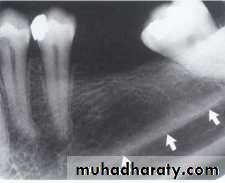

MANDIBULAR CANAL:

The mandibular canal is a tube like passage way through the bone that travels the length of the mandible, its extends from the mandibular foramen to the mental foramen and houses the inferior alveolar nerve and blood vessels. On radiograph the mandibular canal appears as a radiolucent band outlined by two thin radiopaque lines that represent the cortical wall of the canal.

SUB MANDIBULAR FOSSE:

Submandibular fosse is a scooped–out depressed area of bone located on the internal surface of mandible inferior to mylohyoid ridge. On periapical radiography the submandibular fosse appears as radiolucent area in the molars region below the mylohyoid ridge.